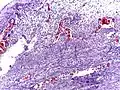

Pathology

Even for clinically certain appendicitis, routine histopathology examination of appendectomy specimens is of value for identifying unsuspected pathologies requiring further postoperative management.[71] Notably, appendix cancer is found incidentally in about 1% of appendectomy specimens.[72]

Pathology diagnosis of appendicitis can be made by detecting a neutrophilic infiltrate of the muscularis propria.

Periappendicitis (inflammation of tissues around the appendix) is often found in conjunction with other abdominal pathology.[73]

Micrograph of appendicitis and periappendicitis. H&E stain

Micrograph of appendicitis showing neutrophils in the muscularis propria. H&E stain

Acute suppurative appendicitis with perforation (at right). H&E stain